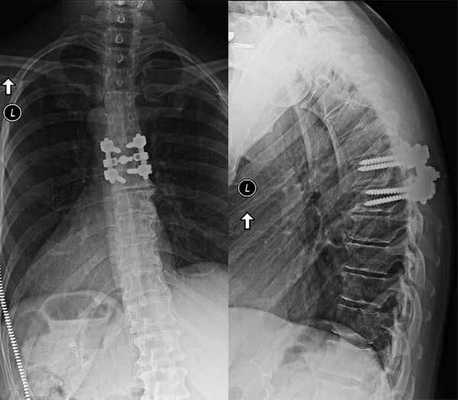

Сагиттальное сечение позвоночного канала после операции измерялось при помощи расчетной программы-локализера ClearCanvas Workstation 2.0. Переднезадний размер позвоночного канала был увеличен в среднем на 0,77±0,23 см (рис. 5 и 6). В трети случаев мы добились увеличения позвоночного канала более чем в 2 раза (рис. 7, 8).

Для исключения сегментарной нестабильности всем больным до операции выполнялось функциональное рентгеновское исследование, в послеоперационном периоде через 3—6 мес выполнялось повторное исследование, не выявившее признаков нестабильности у пациентов нашей группы (рис. 11).